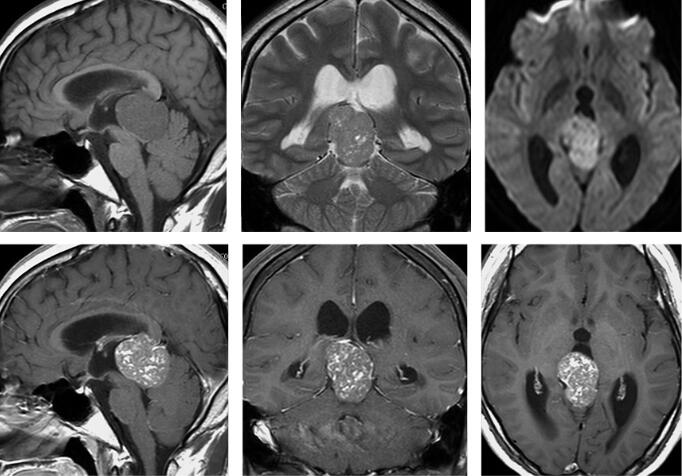

应用Philips Archiva 1.5T超导型MRI扫描系统,8通道头线圈,患者仰卧位。扫描序列包括矢状位T1WI,横断位T1WI、T2WI、FLAIR和DWI,冠状位T2WI。增强扫描行矢冠横断位T1WI扫描,对比剂使用加乐显,7.5ml,经肘静脉手推注射,注射后立即行增强扫描。MRI平扫见图1。

图1 三室后生殖细胞瘤

三室后生殖细胞瘤